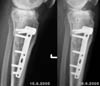

Die aktuellen Röntgenbilder (bitte klicken für grössere Fassungen):

Vergleich 15. August 2005 und 19. September 2005 von vorne

Vergleich 15. August 2005 und 19. September 2005 von der Seite